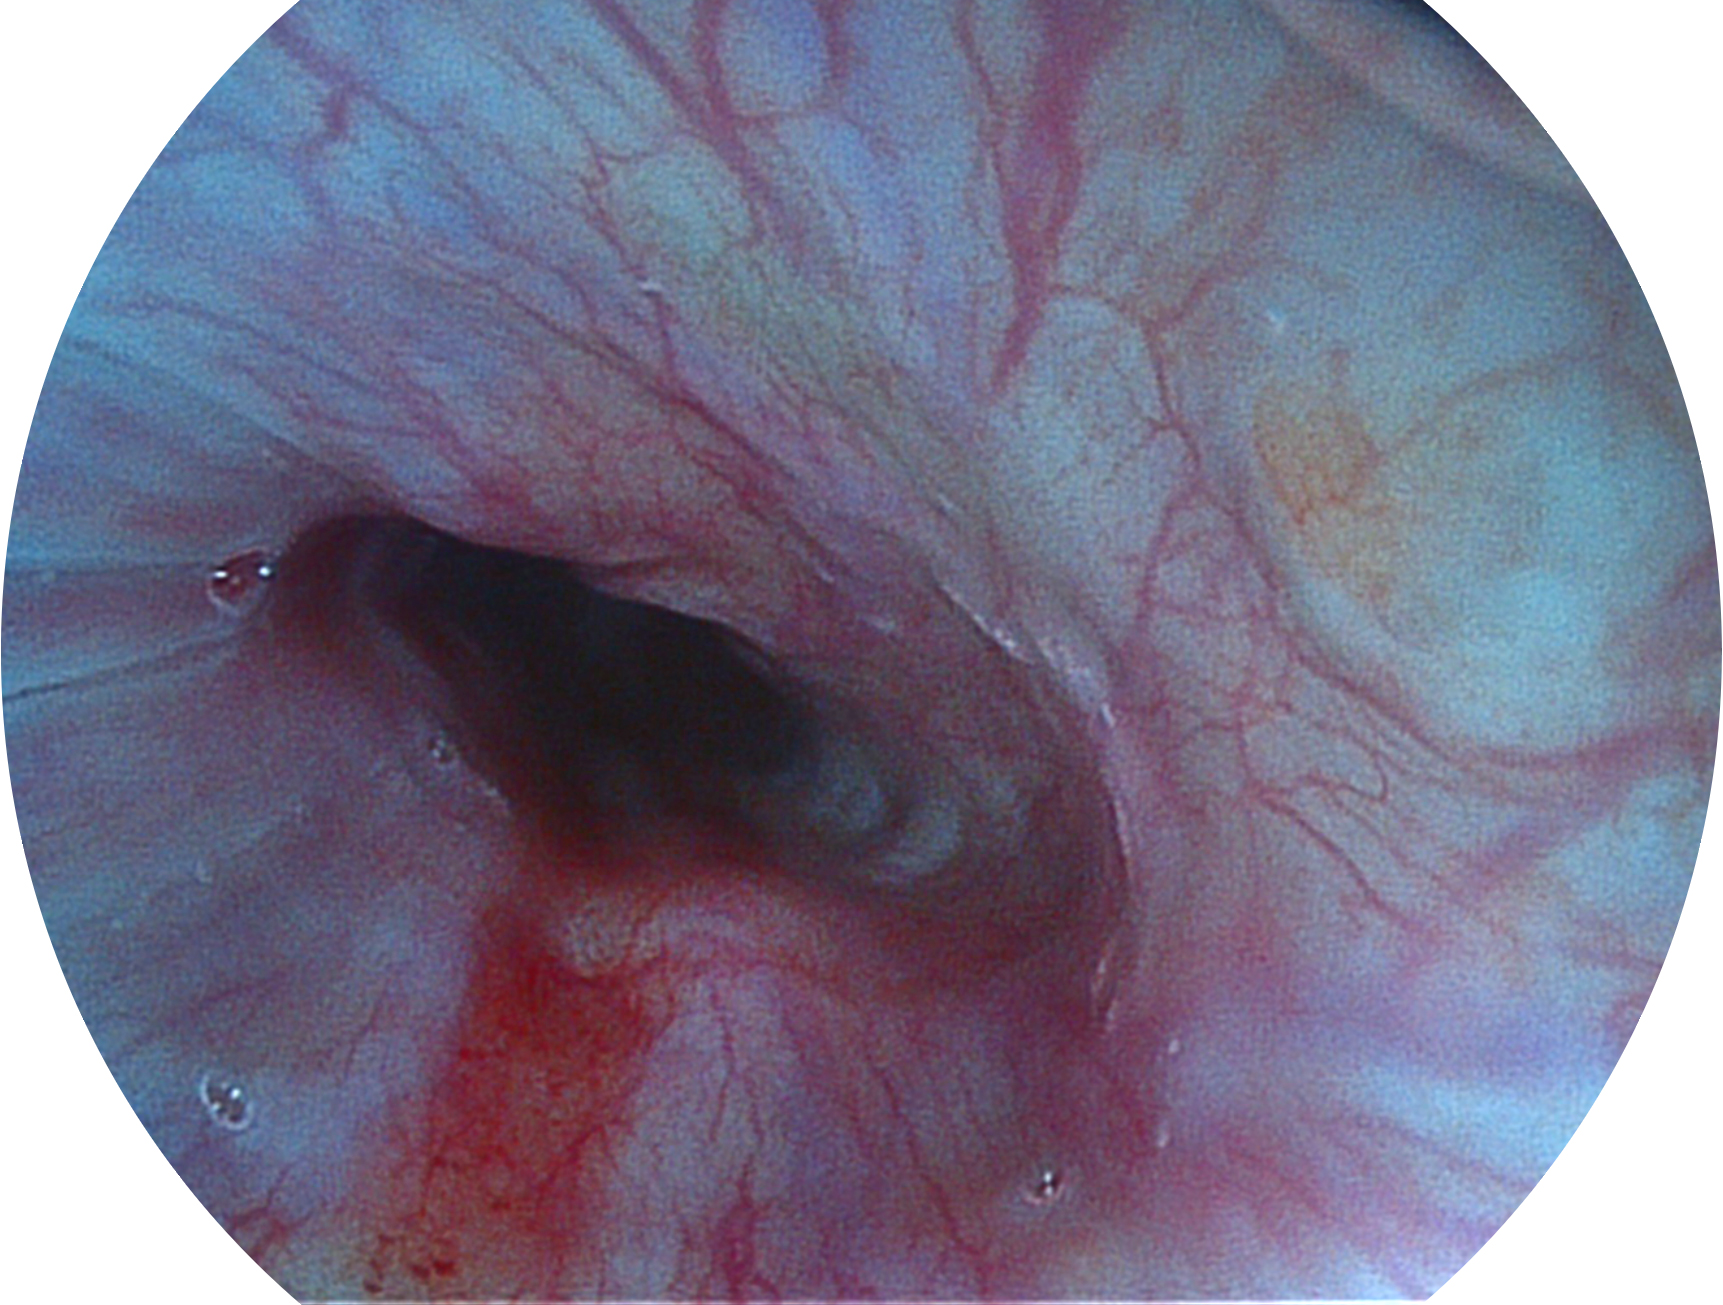

開(kāi)立新開(kāi)發(fā)的內(nèi)鏡染色技術(shù),主要是基于多波長(zhǎng)LED 光源的開(kāi)發(fā),VLS-55Q 四波長(zhǎng)LED 光源是由四個(gè)不同顏色的LED光按照相應(yīng)照明模式所規(guī)定的特定發(fā)光比例進(jìn)行合束后形成,合束后形成的照明光的光譜由紅光、綠光、藍(lán)光及藍(lán)紫光這四個(gè)不同的波段范圍構(gòu)成。具有更高光譜自由度,通過(guò)光譜比例的控制,實(shí)現(xiàn)了聚譜成像技術(shù),英文全稱為“Spectral Focused Imaging, SFI”,縮寫為“SFI”和光電復(fù)合染色成像技術(shù),英文全稱為“Versatile Intelligent Staining Technology, VIST”,縮寫為“VIST”。